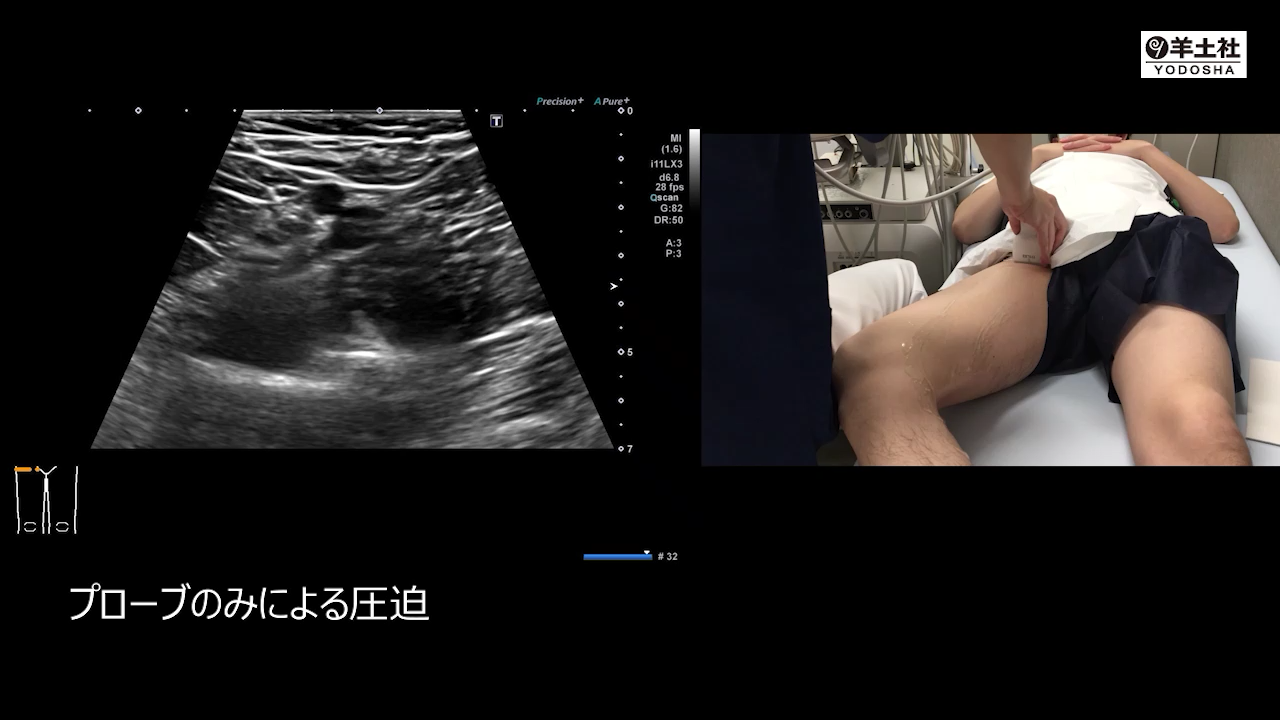

右大腿静脈:圧迫法

「正常像+走査の手元の写真+解剖像」をセットで示し,検査手順や走査方法をコンパクトに解説.実際に検査室で教えてもらっている感覚で読め,検査技術が身につく!プローブ走査とエコー像が連動した動画つき!